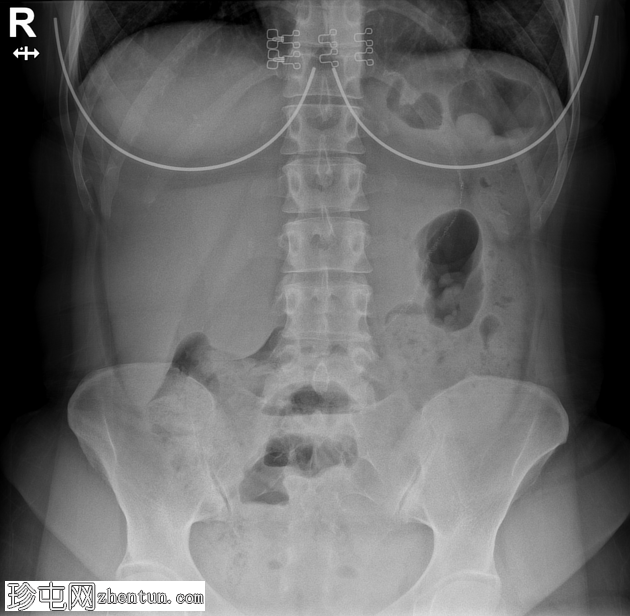

X线片

1.png

多处小肠袢扩张,可见气液平面。

一位既往健康​​的40岁女性因进行性腹痛、腹胀和便秘3天就诊于急诊科。她自述既往有胆囊切除术和剖宫产史。行立位腹部X线片检查,显示多处小肠袢扩张并伴有气液平面。紧急行腹盆部增强CT检查,结果显示闭袢性小肠梗阻伴早期缺血征象。随后行紧急腹腔镜检查,发现粘连带造成梗阻,并证实CT所见的肠缺血,遂行肠段切除吻合术。